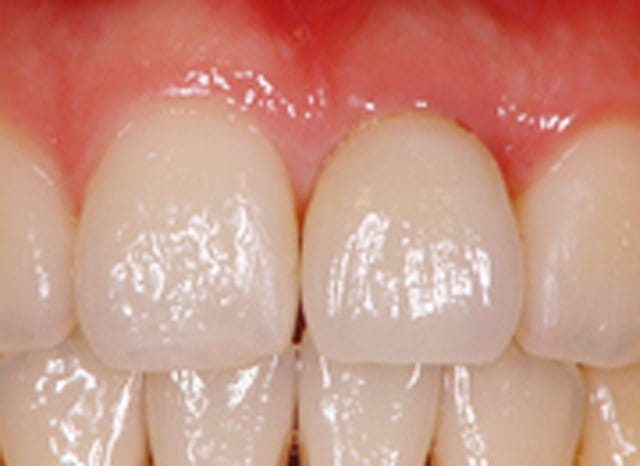

5.仮歯の装着

- 粘膜が治癒したら、インプラントの型取りをして、仮歯(プラスチック)を装着します。

- 仮歯を使ってもらい、違和感や清掃性、歯ぐきの変化等を観察して、最適な形になるように調整を行います。

6.最終補綴装置の装着